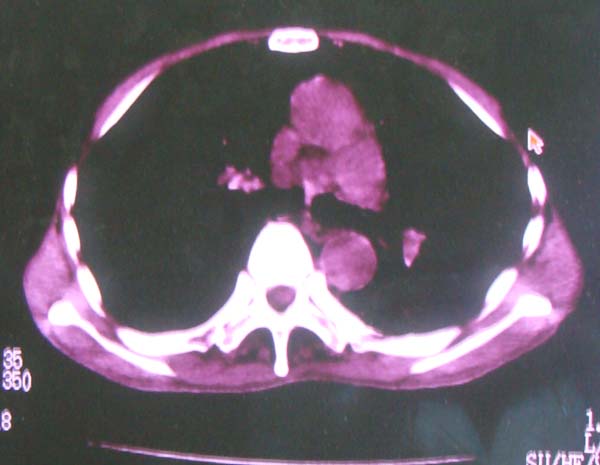

以下是引用zhangzhongshou在2008-2-15 22:25:00的发言:[br]片子照得不清,基本考虑1、细支气管肺泡癌2、亚急性血行播散型肺结核。请结合临床。片子细节显示不清,无法提供进一步意见。

以下是引用杀毒软件在2008-2-15 22:34:00的发言:[br]小叶中心性肺气肿。两肺弥漫性病变,肺泡微石病,过敏性肺炎,尘肺2期,特发性肺纤维化都有可能。[br]不象肺泡癌。